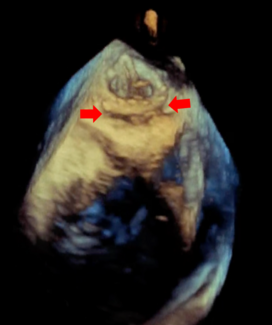

Although the procedure can be done under conscious sedation using transthoracic echocardiographic guidance, it was our preference to use TEE guidance under general anesthesia. After application of general anesthesia, the right internal jugular vein was punctured and a 9 Fr sheath was placed and sutured into place. The CS was intubated with a 9 Fr proprietary delivery catheter (Cardiac Dimensions, Inc) over an AL2 diagnostic coronary catheter (Merit Medical) and a floppy coated .035˝ Radifocus Guidewire M (Terumo Medical Corporation). After removal of the AL2 catheter, a marker catheter was placed (Figure 1), which was used as a scaling device, allowing for measurements of the CS dimensions. The Carillon Mitral Contour System is composed of two self-expanding nitinol anchors, with a curvilinear nitinol connecting section. There are 37 different combinations of distal (7-14 mm) and proximal (16-20 mm) anchor sizes and device lengths (60, 70, and 80 mm) available. After selecting an appropriately sized device, based upon the venous dimensions at the site of each intended anchor and the length of the vein, the device was delivered via the 9 Fr delivery catheter. The distal anchor was delivered into a specified location, based upon distance from the CS ostium, venous characteristics (taper), and relationship to the circumflex coronary artery, since the circumflex artery also passes within the atrioventricular groove, along with the CS. The distal anchor was unsheathed in the desired location within the great cardiac vein, and then locked. After deployment of the distal anchor, slow pulling on the delivery catheter was performed to provide a plicating force on the posterior aspect of the mitral annulus (Figure 2). The intention was to pull approximately 4 cm of tension. Simultaneous imaging with TEE typically demonstrated cinching of the atrial site of the atrioventricular groove as tension was being applied. Coronary angiography was then performed to look for coronary artery compromise by the device. If there was no significant compression or alteration of the circumflex coronary artery and branches, the proximal anchor was released, keeping the device in place by maintaining tension on the catheter and plication on the mitral ring (Figure 3). Right coronary arteriography was then performed, as in rare cases, the distal right coronary artery can be compromised by the proximal anchor.